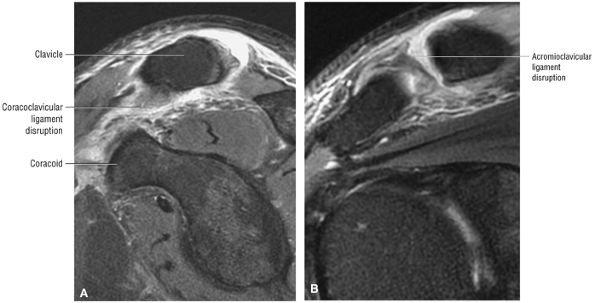

The clavicle connects the axial and appendicular skeletons of the upper extremity.44 It is S-shaped in configuration, with a convex anterior border medially and a concave

P.1195P.1196

anterior border laterally. It is flattened and narrowed laterally and has a thicker cylindrical configuration medially. The clavicle articulates with the sternoclavicular joint medially and with the AC joint laterally (Fig. 8.57). The surfaces of the sternoclavicular joint are covered by fibrocartilage, and a fibrocartilaginous articular disk divides the joint into separate recesses.45 -

The coracoclavicular ligaments are also displayed on anterior coronal oblique images. The anatomy of the AC articulation is best displayed at the level of the supraspinatus tendon. When present, AC joint fluid may represent an asymptomatic manifestation of osteoarthritis.41